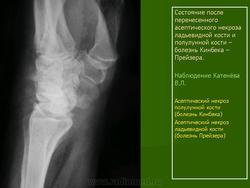

Остеохондропатия. Прейзера болезнь. Паннера болезнь. +

Прейзера болезнь (m,Preiser), остеохондропатия ладьевидной кости кисти, остеомаляция ладьевидной кости, остеохондрит ладьевидной кости. Описана немецким ортопедом Preiser G. К. в  1911 г. Относится к группе остеохондропатий. Клинически проявляется болью, ограничением движений в лучезапястном суставе, боль усиливается при сжатии пальцев в кулак. Рентгенологически определяется уплотнение ладьевидной кости, неравномерность ее структуры, наличие мелких кист. Эти изменения иногда напоминают картину перестройки ладьевидной кости после ее перелома.